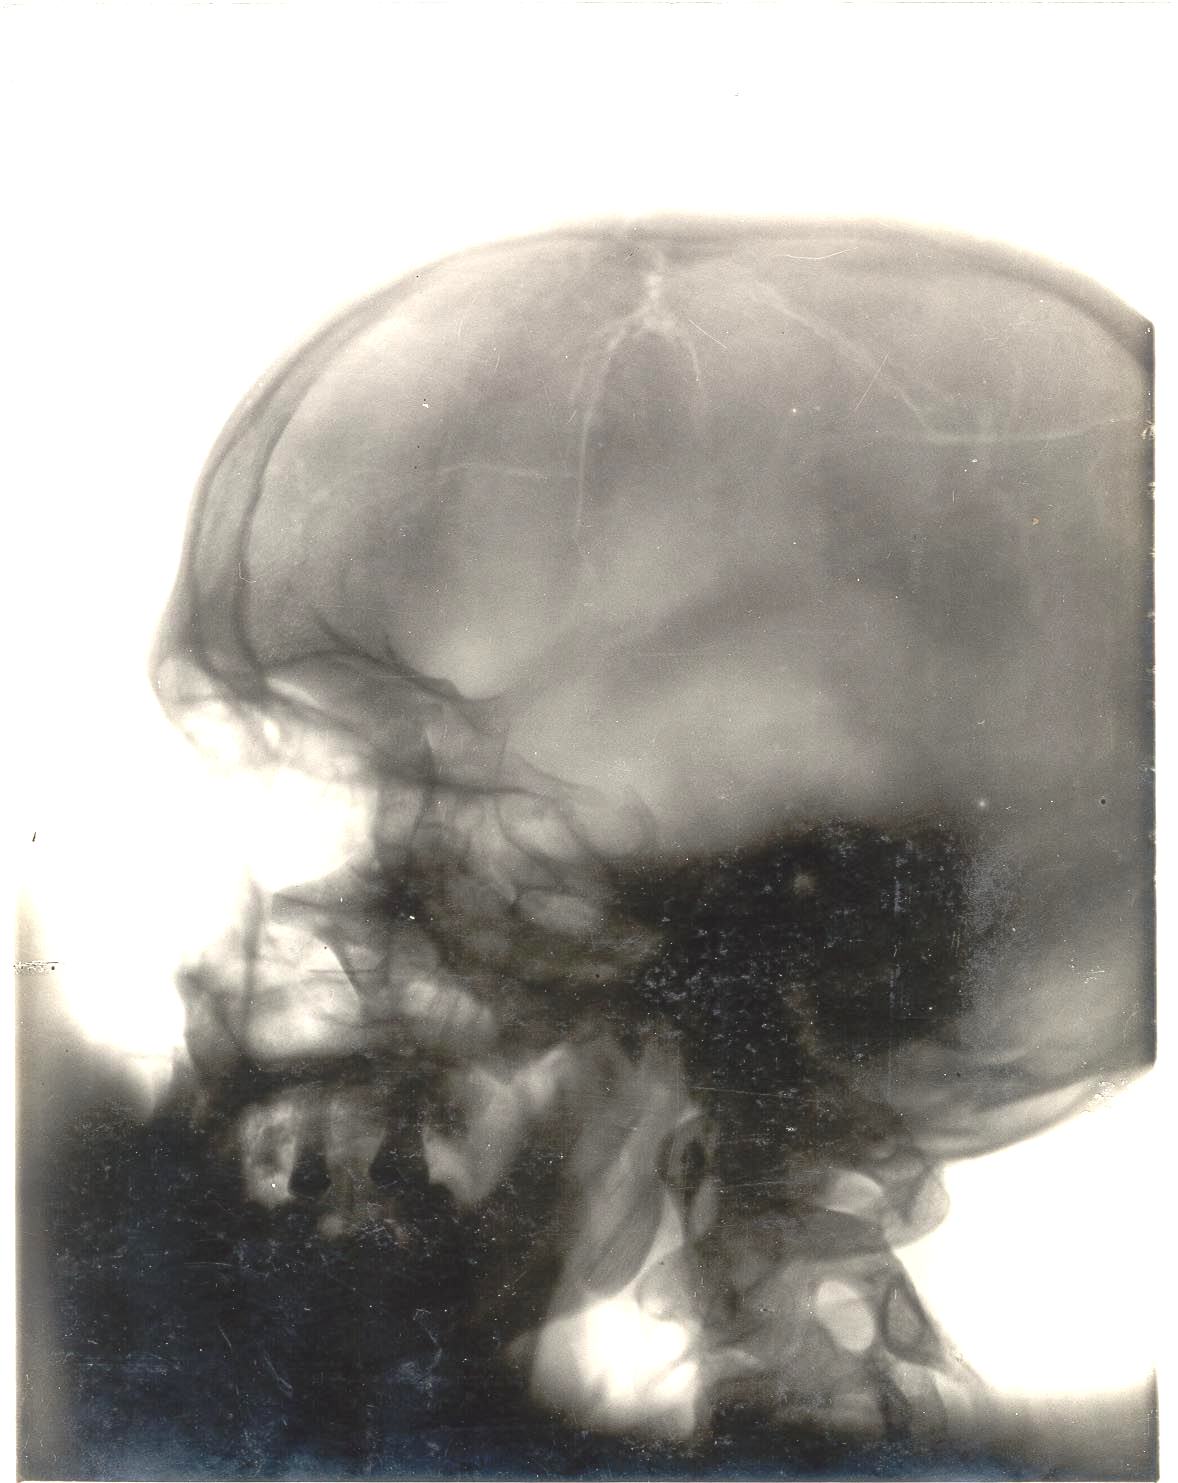

Andre Waters

Height: 5-11 Weight: 200 Born: 1962-03-10; Belle Glade, FL College: Cheyney Draft: None